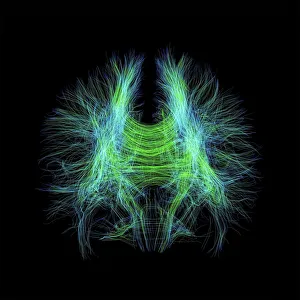

The central nervous system, the intricate network that governs our every thought and movement, is a marvel of complexity. From the delicate cerebellum tissue to the detailed light micrograph capturing its essence, we are reminded of its importance in maintaining balance and coordination. Anatomy comes alive as we explore the human brain from an inferior view. The intricacy of brain fibers is revealed through DTI MRI scans like C017/7099 and C017/7035, showcasing their vital role in transmitting information throughout this extraordinary organ. Artistic renderings bring us closer to understanding the medulla oblongata's significance within the brain. Its portrayal in various artworks allows us to appreciate how it controls essential functions such as breathing and heart rate. As we delve deeper into studying the central nervous system, models of the human brain provide invaluable insights into its structure and organization. Lateral views reveal countless regions responsible for cognition, emotion regulation, sensory perception, and motor control. Microscope slides offer glimpses into nerve cells' intricate architecture—a testament to their ability to transmit electrical signals at lightning speed. Meanwhile, glial stem cell cultures captured under a light microscope remind us of their crucial role in supporting neuronal function. Finally, artistic representations unveil the limbic system's enigmatic nature—an interconnected web responsible for emotions and memory formation. These captivating artworks allow us to visualize this complex network within our brains. Exploring these hints provides a glimpse into the awe-inspiring world of our central nervous system—the very foundation upon which our thoughts, actions, memories reside—reminding us just how remarkable our brains truly are.